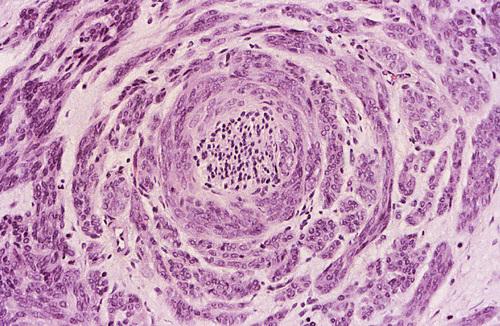

Islands of hyperchromatic cells forming cribriform and tubular structures. Inset shows a high-power view of a small cribriform island. The cribriform pattern is the most classic appearance, characterized cystlike spaces resembling Swiss cheese.

adenoid cystic carcinoma

The tumor cells are surrounded by hyalinized material. In the tubular pattern, the tumor cells are similar but occur as multiple small ducts or tubules within a hyalinized stroma.

adenoid cystic carcinoma

Perineural invasion. This is a highly characteristic feature of this tumor, probably corresponding to the common clinical finding of pain in these patients.

adenoid cystic carcinoma